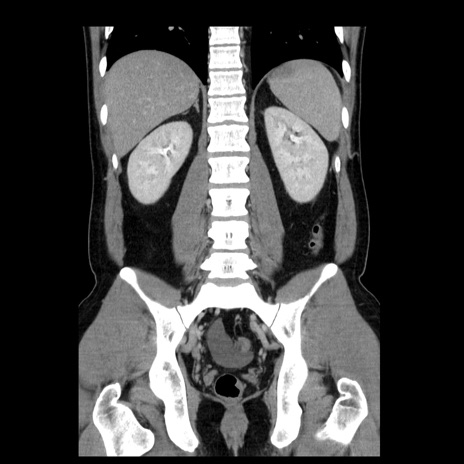

症例4(冠状断像)

【症例】30歳代男性

【主訴】腹痛、嘔吐

【現病歴】昨晩から突然の腹痛あり、その後嘔吐、軟便も出現。腹痛が改善しないため救急搬送となる。2日前にしめ鯖の食事歴あり。

【身体所見】意識清明、苦悶様、BP 135/90mmHg、BT 35.7℃、腹部:平坦、やや硬、心窩部〜臍部に自発痛、圧痛あり、筋性防御+、反跳痛-

【データ】WBC 8100、CRP 0.57